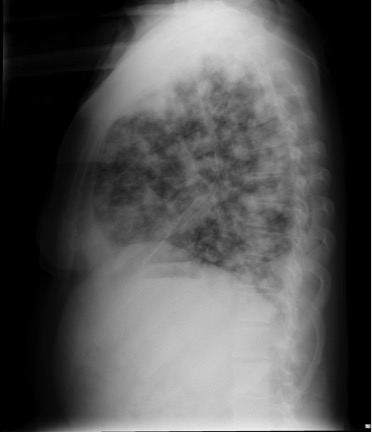

CASO: Paciente inmunodeprimido con Disnea.

Hallazgos:

- En la placa PA hay opacidad difusa bilateral de ambos hemitorax en vidrio deslustrado. En bases pueden intuirse opacidades mutifocales. La placa lateral también muestra la opacidad total del parénquima.

IMPORTANTE: Estos hallazgos son inespecíficos, pero ante un paciente inmunodeprimido, la evidencia de opacidad en forma de vidrio deslustrado, más aun si es de predominio perihiliar y en lóbulos superiores, hay que descartar en primer lugar una neumonía por Neumocistis, que en nuestro medio suele vincularse a pacientes VIH positivos.

VIDRIO DESLUSTRADO: Aumento de densidad difusa que no impiden la visualización de los vasos pulmonares que contienen. Se puede ver en afectación del espacio aéreo y/o del intersticio.

Causas:

- Infecciosas (P.Jiroveci y CMV)

- Neumonía intersticial descamativa.

- Alveolitis alérgica extrínseca.

- Sarcoidosis.

- Neumonía intersticial habitual.

- Proteinosis alveolar.

- Neumonía organizada criptogénica